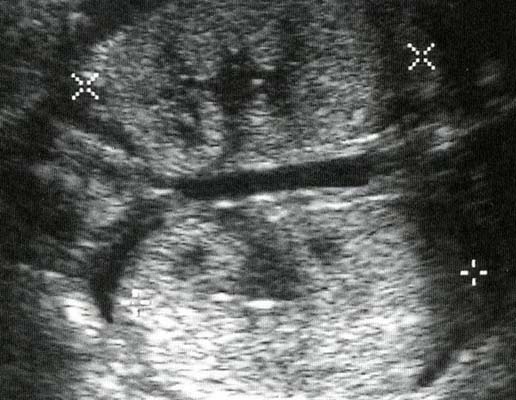

Echographiquement :

- Kystes de taille variable de 1 à plusieurs centimètres, en nombre variable, non communiquant entre eux, réparties anarchiquement au sein du rein dont les contours sont bosselés.

- Echogénicité du parenchyme résiduel.

- Formes sévères : Oligoamnios sévère précoce évoluant vers l’anamnios.

- Hypertrophie compensatrice du rein controlatéral.